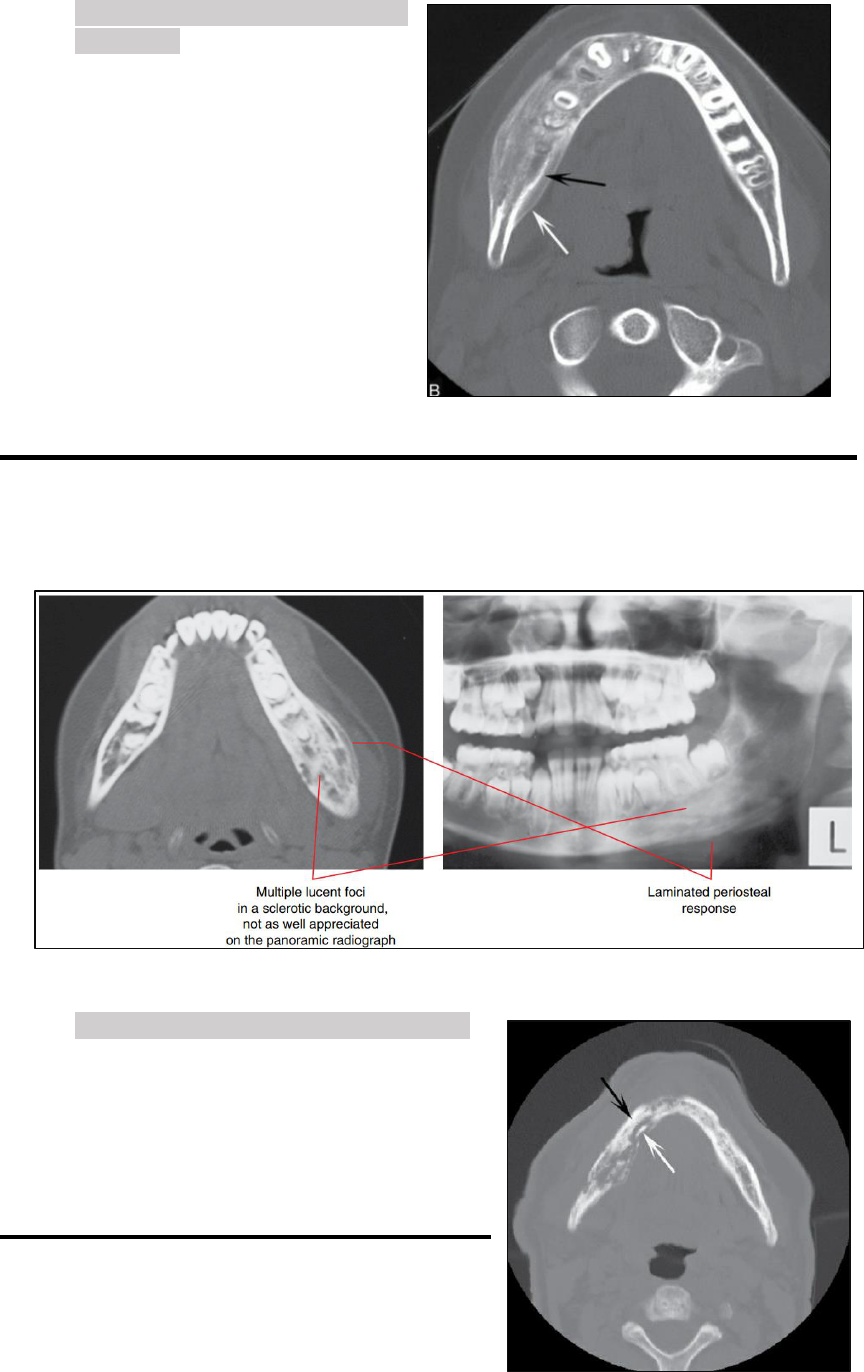

Importância dos aspectos imaginológicos no plano de tratamento da displasia óssea florida: Relato de caso

Grátis: ASPECTO RADIOGRAFICOS DAS LESÕES FIBRÓSSEAS E OSTOMIELITES - Material Claro e Objetivo em PDF para Estudo Rápido